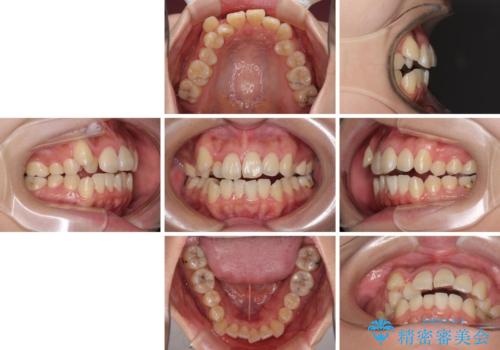

- 八重歯と叢生を気にして来院された患者様です。

上下の前歯が非接触であり、叢生や八重歯が顕著であったため、上顎左右第一小臼歯2本を抜歯して排列することとしました。

抜歯により移動量が多くなるため、ワイヤーや補助装置を活用し、その後インビザラインによる矯正治療を行うこととしました。

元々奥歯に負担のかかる咬み合わせですり減っていたため、仕上がった歯並びでも奥歯が咬んでいないように見えましたが、実際にはしっかりと咬合しており、患者様本人も咬んだ感触に違和感はないとのことでした。